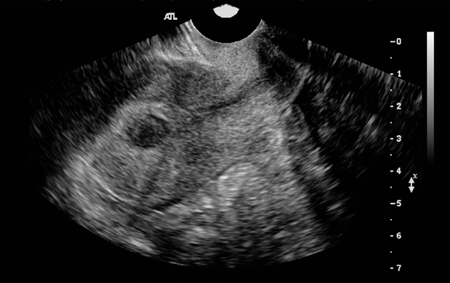

Transvaginal pelvic ultrasound (TVUS) shows a midline posterior fundal fibroid greatly distorting the endometrial cavity

From the personal collection of Dr M.F. Mitwally and Dr R.J. Fischer; used with permission